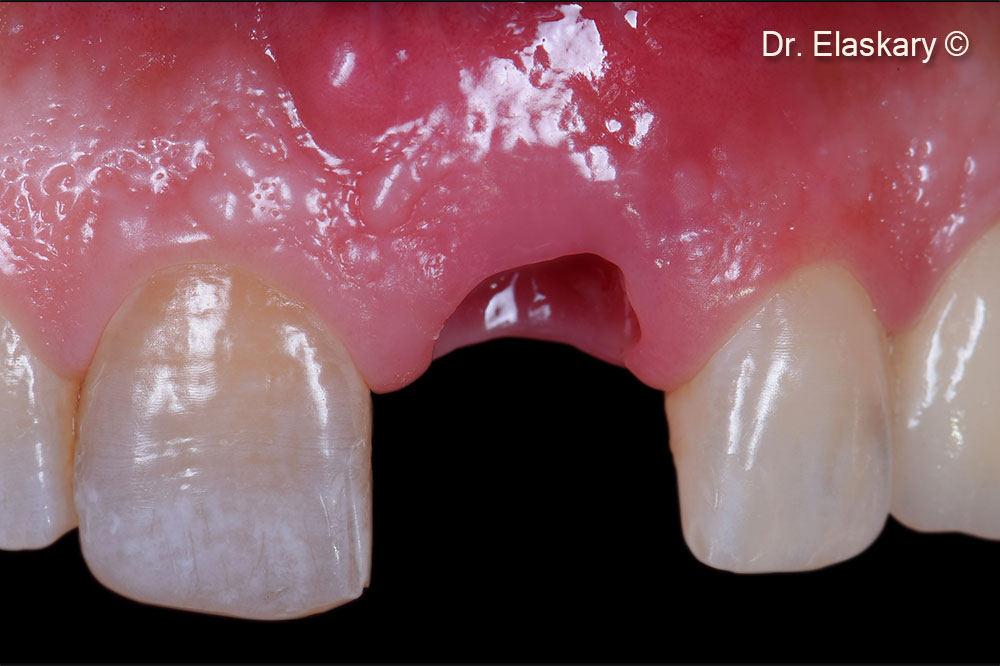

Frontal view of the location after the tooth is extracted and the socket debrided